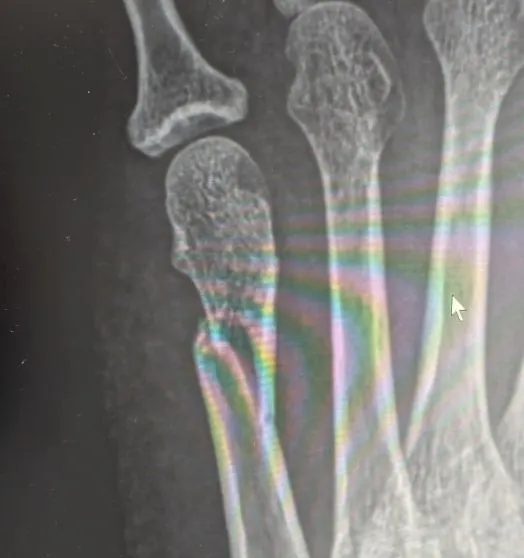

但回家的路上,覺得腳越來越不對勁,回到家,請老公下來拿菜,我完全不敢再動,連忙請老公帶我去骨科診所,想說照個X光確認一下比較保險。照了X光後,我最不能接受的結果發生了——我的腳的第五蹠骨骨折了,醫生說有位移,還有一些碎片,非開刀不可,我聽了冷汗直流,骨折的X光片我到現在還不忍直視,沒想到一個小跌倒,會有這麼嚴重的傷害。